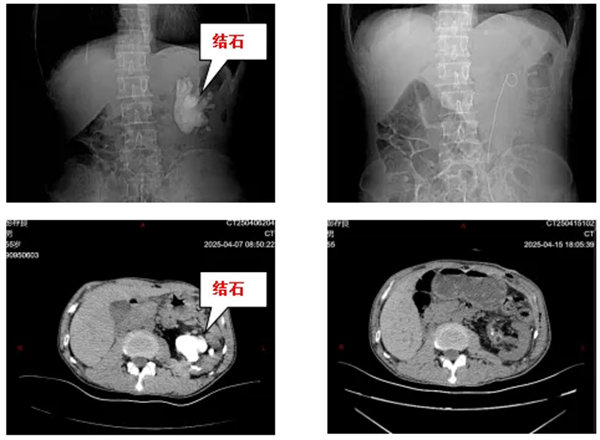

近日,寶雞市人民醫院泌尿外一科接診了一位特殊患者。張先生(化名)因持續腰痛就醫,檢查結果令人震驚:該患者只有一個腎,且唯一的左腎內竟藏有一個直徑達8cm的巨型鑄型結石,形如“鹿角”般盤踞整個腎盂系統,且質地異常堅硬,與腎盂黏膜緊密粘連。對于獨腎患者而言,這不僅關乎疼痛,更是一場生死考驗!

經過3小時的精細操作,醫療團隊成功完整取出所有結石分支。術后檢查顯示患者腎盂系統通暢,腎功能指標穩定。患者術后恢復順利,術后一周即康復出院。